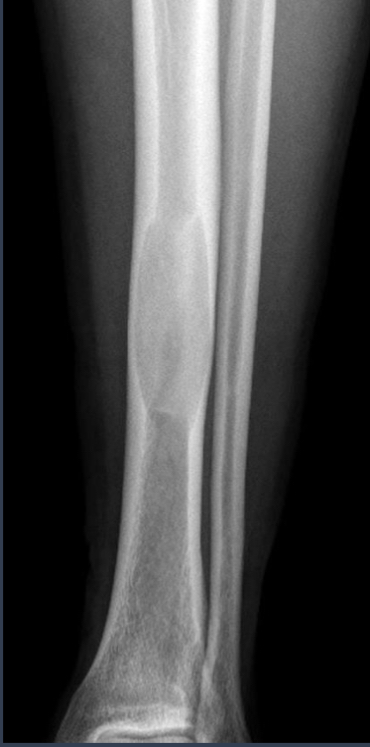

how do you describe this?

what is it?

ground glass

fibrous dysplasia